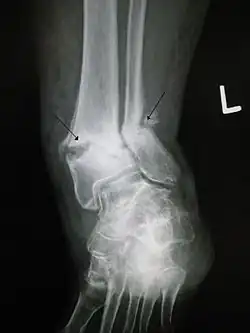

A bone fracture may be diagnosed based on the history given and the physical examination performed. Radiographic imaging is often performed to confirm the diagnosis. Under certain circumstances, radiographic examination of the nearby joints is indicated to exclude dislocations and fracture-dislocations. In situations where projectional radiography alone is insufficient, Computed Tomography (CT) or Magnetic Resonance Imaging (MRI) may be indicated.

| Diagnostic method | X-ray, computed tomography, MRI |